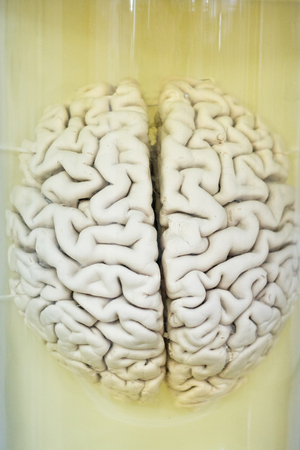

Human brain in formalin solution closeup